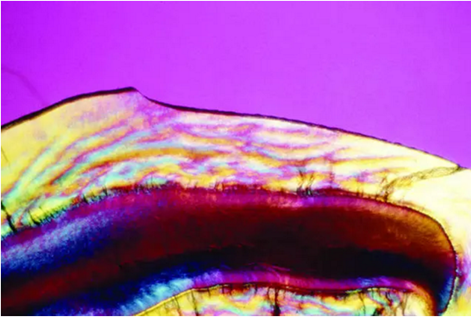

是在同一时期萌出的釉质上有白垩色到褐色的斑块,严重者还并发有釉质的实质缺损。临床上常按其轻、中、重度而分为白垩型(轻度)、变色型(中度)和缺损型(重度)三种类型:

(1)白垩型(轻度) 牙面失去正常光泽,出现不透明斑块;

(2)变色型(中度) 牙面出现黄色、黄褐或棕褐色;

(3)缺损型(重度) 除上述改变以外,牙面还出现浅窝或坑凹状缺损,或因磨损使牙失去正常外形。

1.牙釉质发育不全白垩色斑的周界比较明确,而且其纹线与牙釉质生长发育线相平行吻合;氟牙症为长期性的损伤,故其斑块呈散在的云雾状,周界不明确,并与牙釉质生长发育线不相吻合。